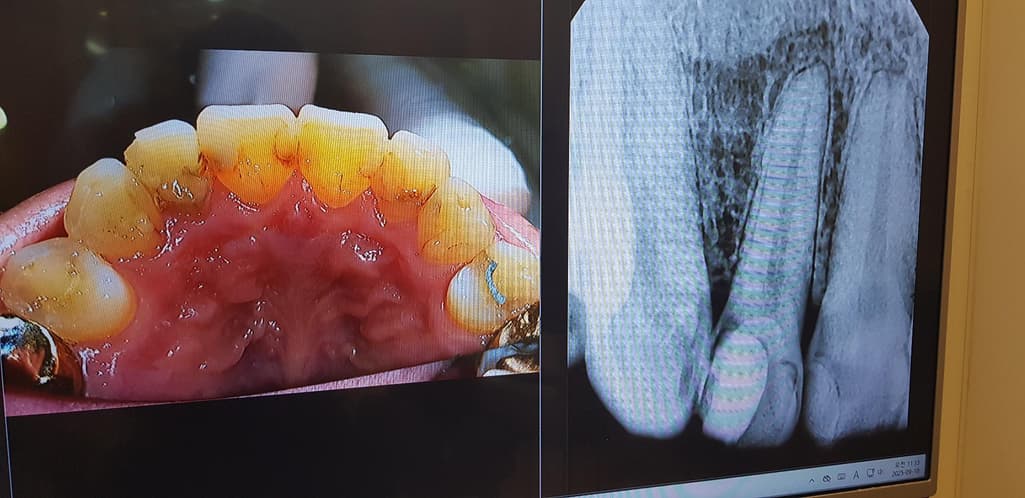

저 11번 파절된 치아가 충치 상태인지

충치 상태라면 육안으로 보이는 부위인지

충치 진행도는 어느정도인지 궁금하네요.

사진에 보이는정도면 기존 수복물을 제거하게되면 신경치료를 하셔야될것같습니다. 엑스레이 상으로는 충치가 상당히 깊어 보입니다.

사진으로 봤을 때 치아 주변으로 많은 부위가 충치 이환된 것으로 보입니다. 충치를 제거했을 경우 신경이 노출될 수 있으며 신경치료를 하고 나서도 크라운을 지지할 힘이 약하다면 기둥을 제작해야 할 수 있습니다.

12(측절치),13(송곳니)번 치아는 육안이나 방사선 사진상으로나 충치가 있어보입니다. 특히 12번은 애초에 깊은 충치를 신경치료 없이 떼워둔 상태인데 하방으로 충치가 있어서 신경치료 가능성도 있을 것 같습니다